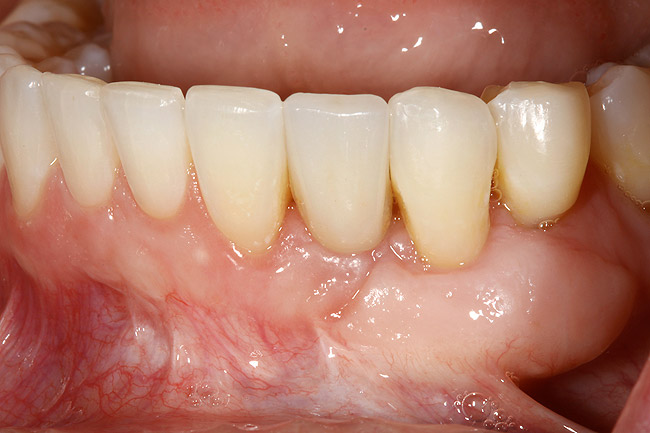

Figure 24  Definitive restoration of tooth No. 23.

Figure 24

Figure 25  Postoperative view of definitive restorations teeth Nos. 7 to 9 and No. 23.

Figure 25